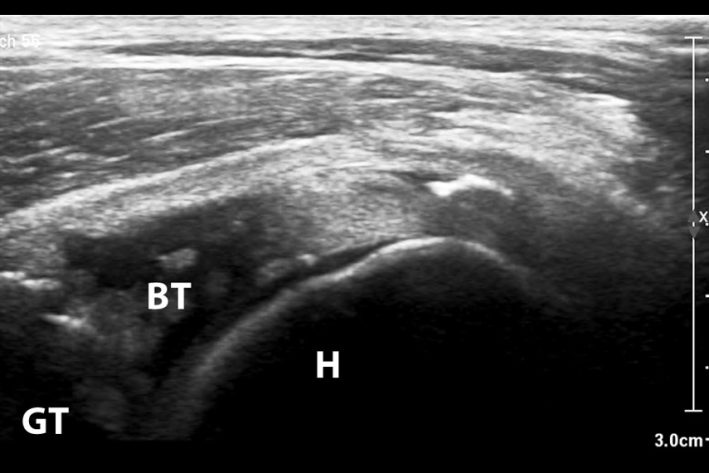

Die klinische Untersuchung liefert einen ersten Hinweis auf eine Schultergelenkserkrankung. Zur weiteren genauen Diagnosestellung wird meist eine Kombination aus Ultraschall und CT durchgeführt. Eine Entzündung und auch eine Teilruptur wird hier in den meisten Fällen erkannt. Bei einer Luxation kann die Diagnosestellung schwieriger sein, da sich die Sehne nicht immer in der luxierten Position befinden. Der Goldstandard zur Diagnostik ist in unklaren Fälle die Arthroskopie des Schultergelenkes.